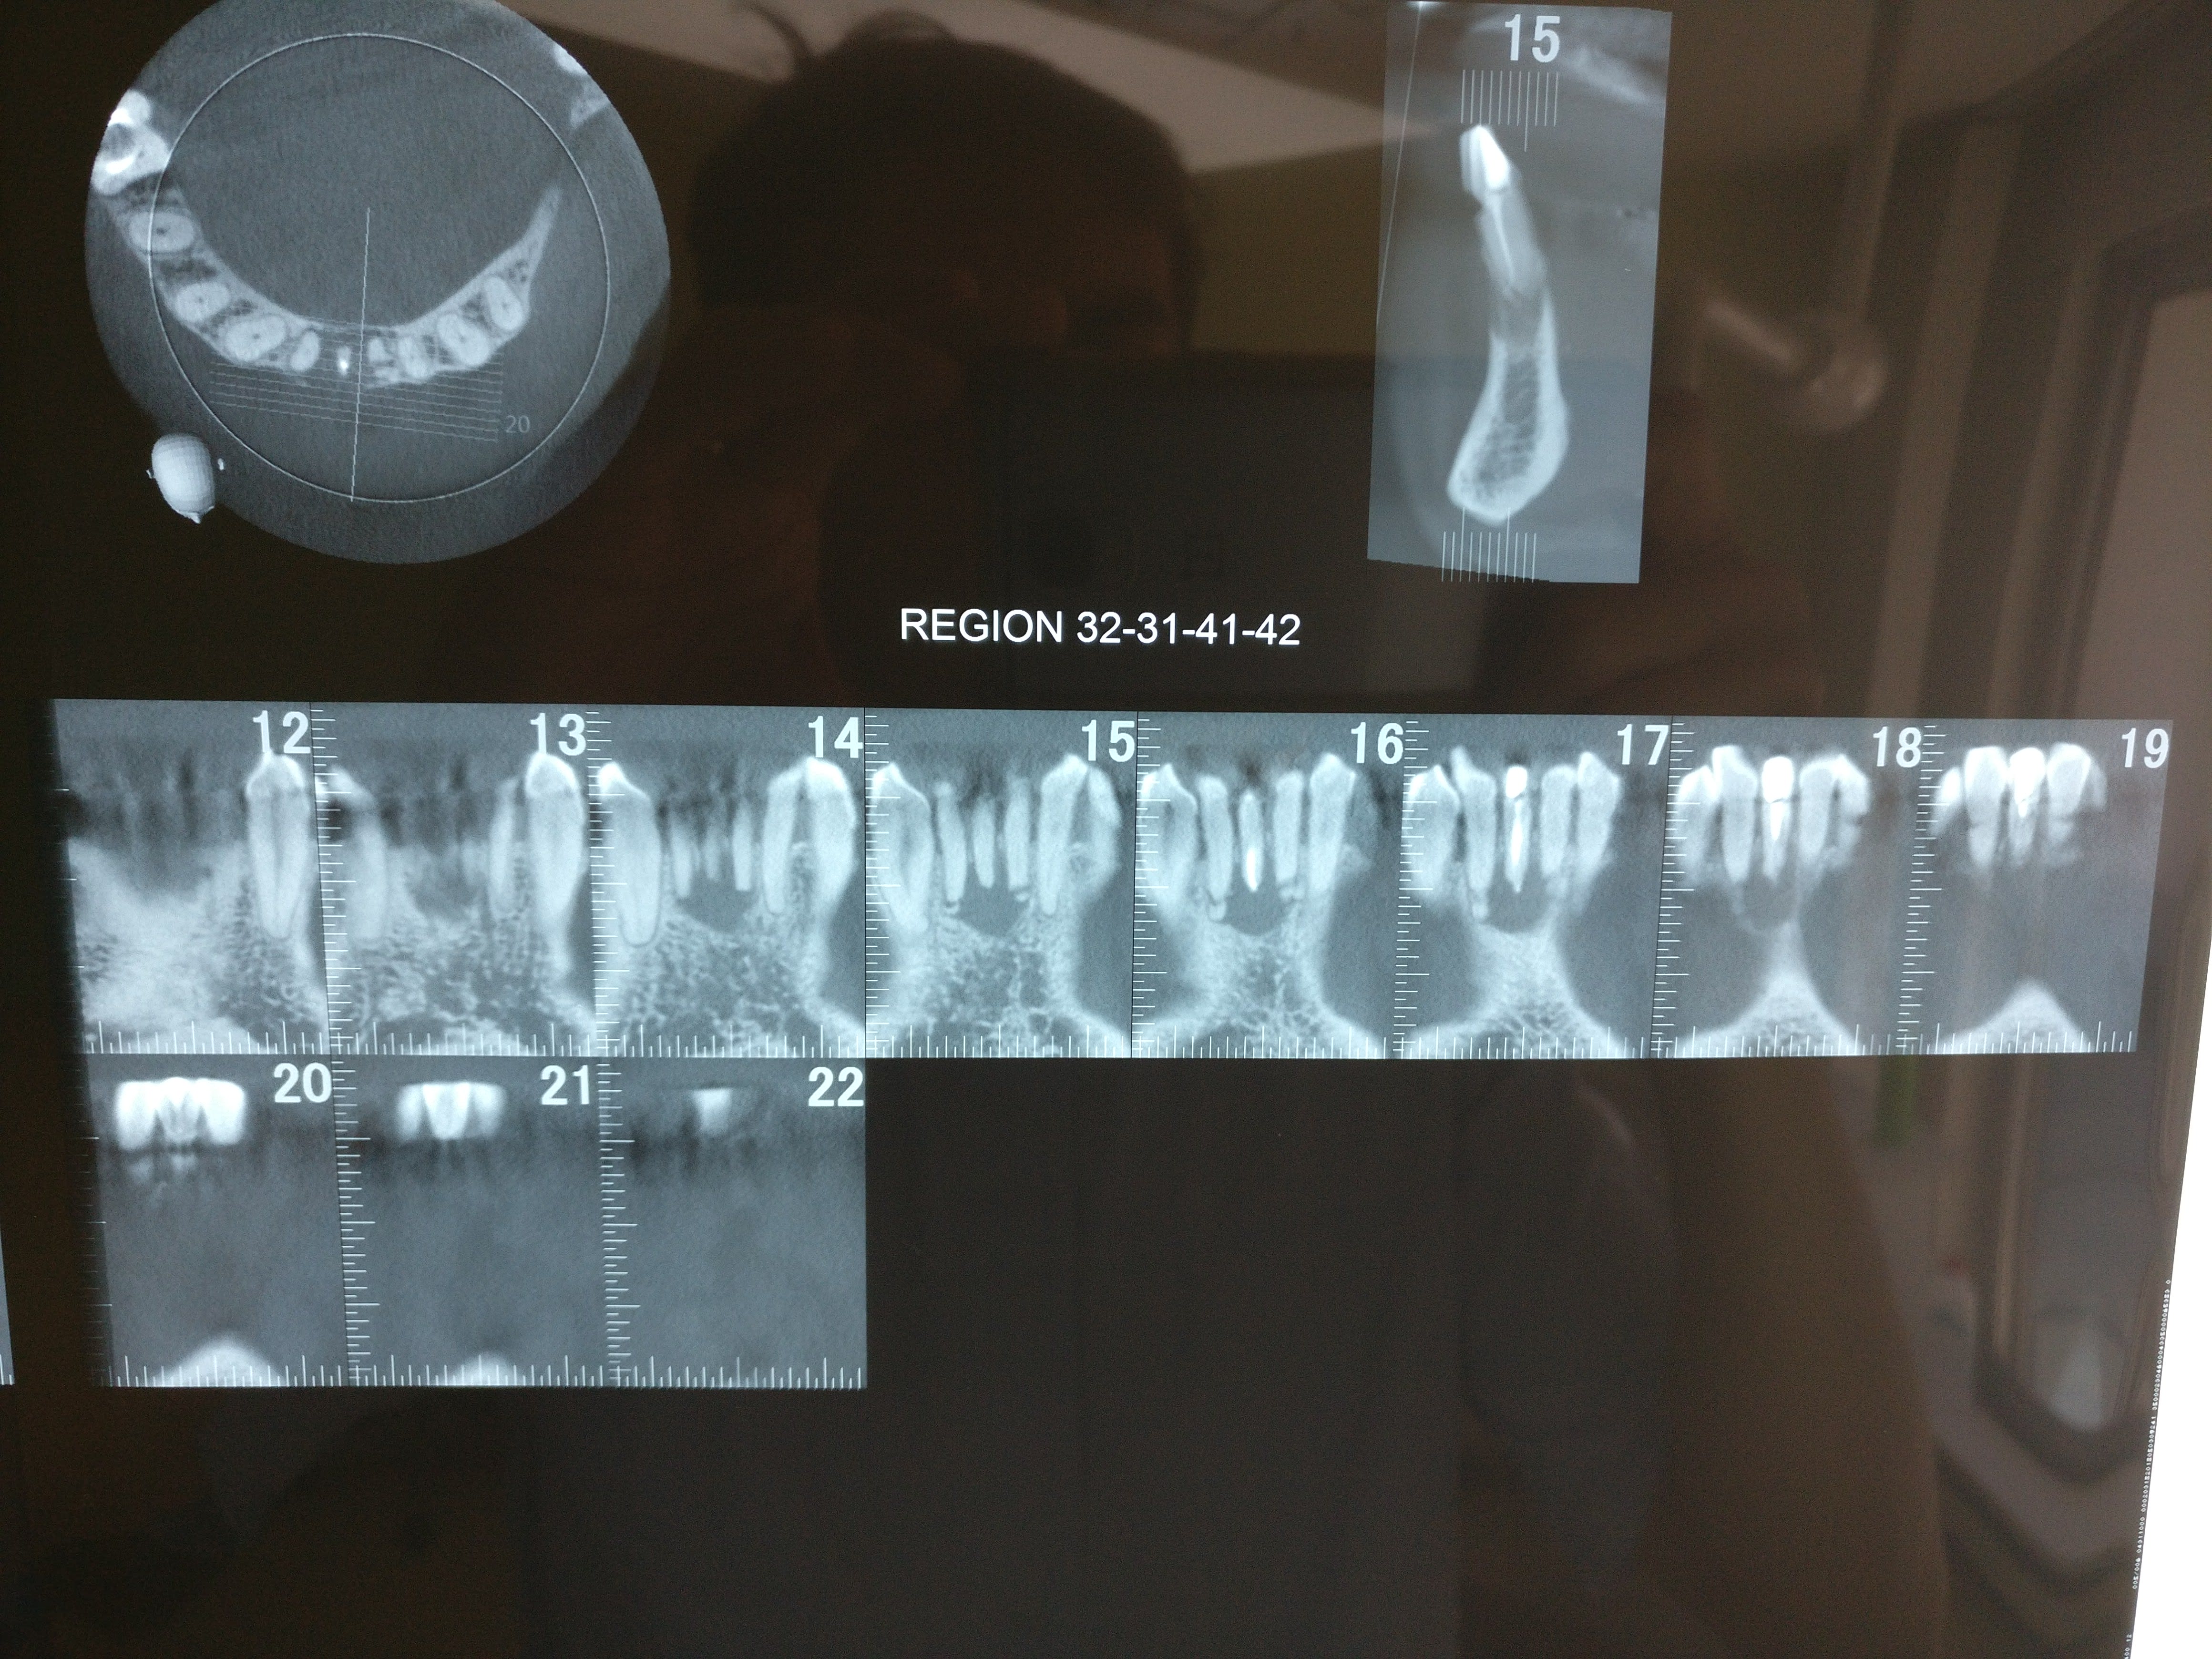

En fait, ce qui m'a induit en erreur, c'est la coupe 15 du doc 3, je ne comprends pas son orientation. L'image est très différente des coupes du doc 4.

(elle est en rotation de manière importante la 31?)

D'ailleurs, c'est une 41.

Je pense que j'ai compris, je pense que tu devrais trouver le second en linguo distal.

A la base je pense qu'il y avait un second canal en lingual. Regarde les coupes horizontales tu devrais le trouver ou au moins l'imaginer. Sur les coupes sagittales, le canal que tu as obture est deporte en vestibulaire, c'est une bonne indication. Sur la retro tu vois bien les deux racines de l'incisive latérale, tu trouves en general 2 canaux sur la centrale dans ce cas la.